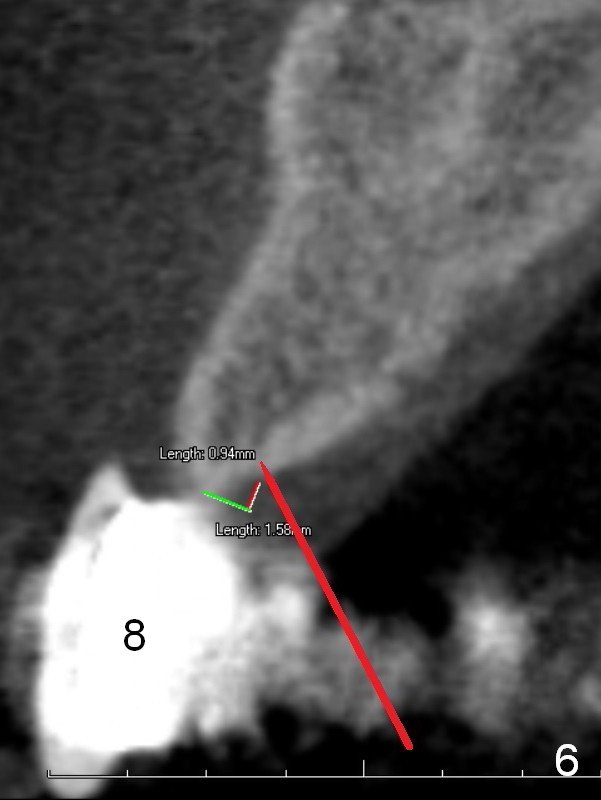

A 60-year-old man is partially edentulous; A 6-unit (#6-10) bridge has been in function for more than 10 years (Fig.1). The connection between #8 and 9 pontics breaks lately. The edentulous ridges are narrow (Fig.2-5), especially at #7 and 10. One piece implants (2.5x14 and 3x14 mm) are planned to be placed at the lateral and central incisor sites, respectively. They should be placed as palatal (P in Fig.2) as possible.

For example at the site of #8 (Fig.6), start osteotomy 1 mm palatal to the crest (red line). As the first pilot drill (1.2 mm) enters the cortex, the trajectory is changed (Fig.7 green curved arrow).